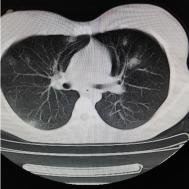

性别:女,年龄:26岁,低热,轻微胸痛,支原体阳性

[影像描述]

两肺内及胸膜下多发斑片状高密度影,部分病灶密度较淡,部分实变,边缘可见渗出改变。